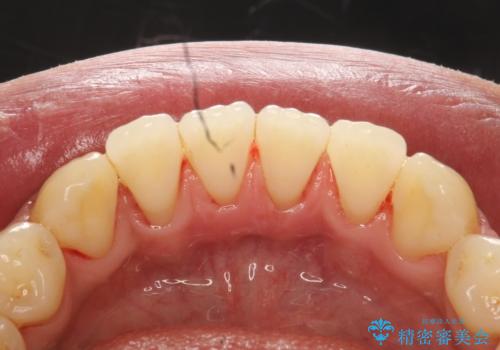

下の歯の裏側の着色

前歯のステイン(着色)をPMTCでキレイに

1年ぶりのPMTCで着色落とし